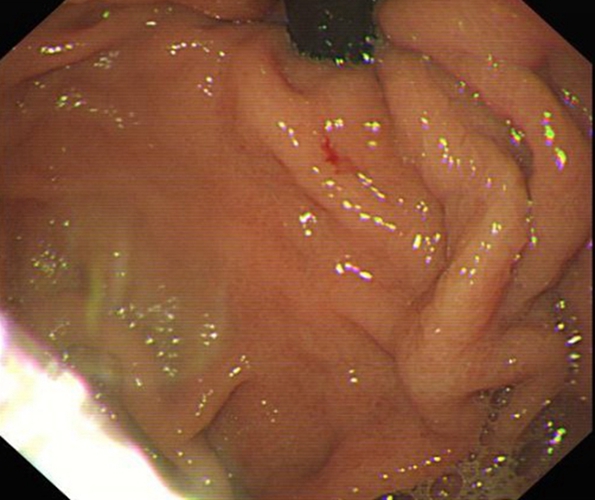

急性胃炎圖片

急性胃炎

急性胃炎胃部